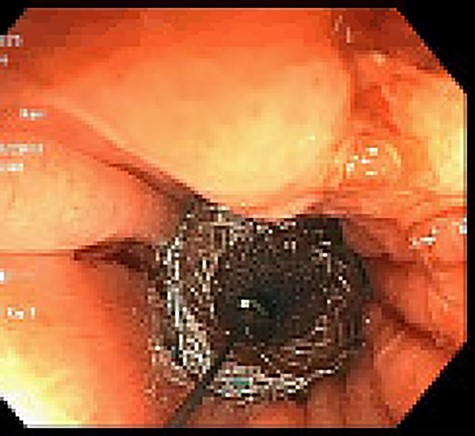

Approximately 2 months into his postoperative course, he returned with symptoms of dysphagia. esophagogastroduodenoscopy (EGD) revealed benign-appearing stenosis at the level of the esophagogastric anastomosis. This was initially dilated with a balloon. However, due to recurrent symptoms, a fully covered SEMS was placed to alleviate stricture (Figs 1, 2). The patient did well for nearly 2 months before returning with recurrent symptoms. A new web was visualized causing complete luminal obstruction (Fig. 3). This was unable to be traversed in antegrade fashion, requiring retrograde access via the jejunostomy utilizing guidewire. A pediatric colonoscope was able to be passed over the guidewire and dilate before subsequent SEMS deployment (Fig. 4). This stent was secured using 2-0 polypropylene suture via Overstitch device (Fig. 5). The initial SEMS was found to have migrated to the mid portion of the gastric conduit. However, due to the small caliber of the proximal stricture and to avoid disrupting newly deployed stent, the initial SEMS was left in place.